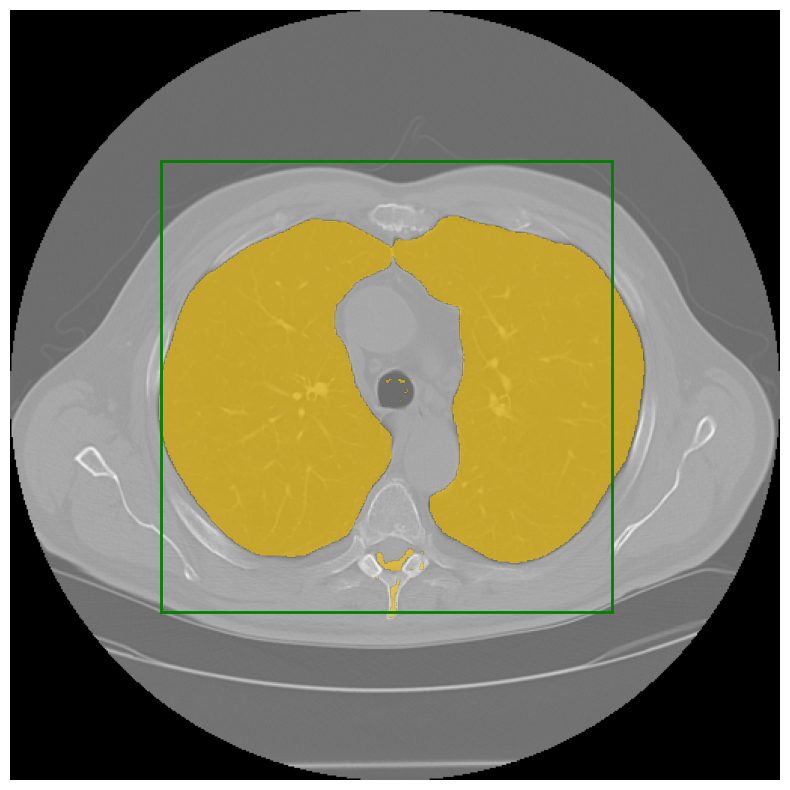

SAM-Medical-Imaging: Segment Anything Model (SAM) native Qt UI (Project) Jordão Bragantini, Kyle I S Harrington, Ajinkya Kulkarni |  | [Github] |